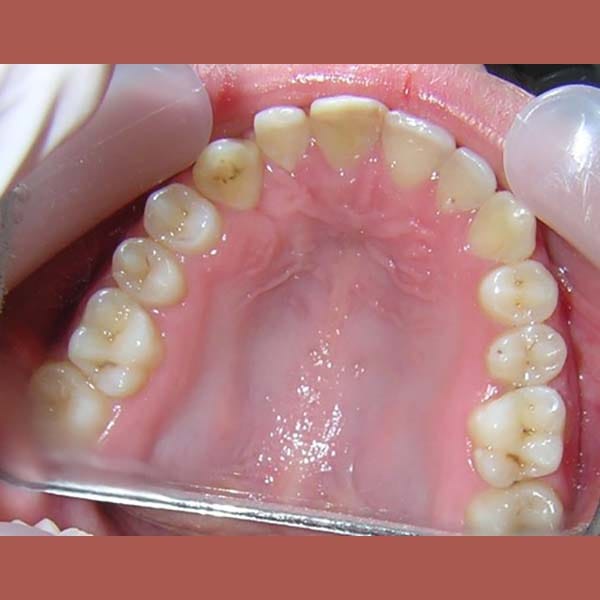

AFTER

كما تظهر الصور، تم إنزال الناب المنطمر بنجاح ورصفه بشكل مثالي مع بقية الأسنان. النتيجة هي ابتسامة كاملة وصحية، واستعادة سن مهم جداً لوظيفة الفم وجمال الابتسامة.